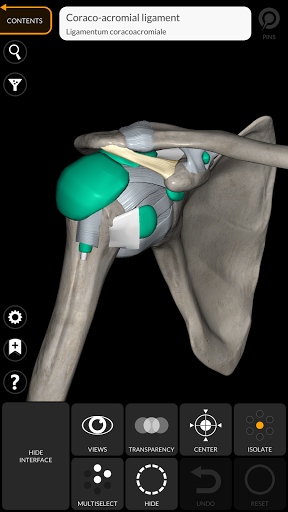

"Anatomy 3D Atlas" дозволяє легко та інтерактивно вивчати анатомію людини.

Завдяки простому та інтуїтивно зрозумілому інтерфейсу можна спостерігати кожну анатомічну структуру під будь-яким кутом.

Анатомічні 3D-моделі особливо деталізовані та мають текстури з роздільною здатністю до 4k.

• Кістково-м’язова система

• Можливість приховування або ізоляції однієї чи кількох вибраних моделей

• Вибравши модель або шпильку, з’явиться відповідний анатомічний термін

Ліги додані